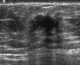

Extraabdominal desmoid tumor

Chest wall lesion